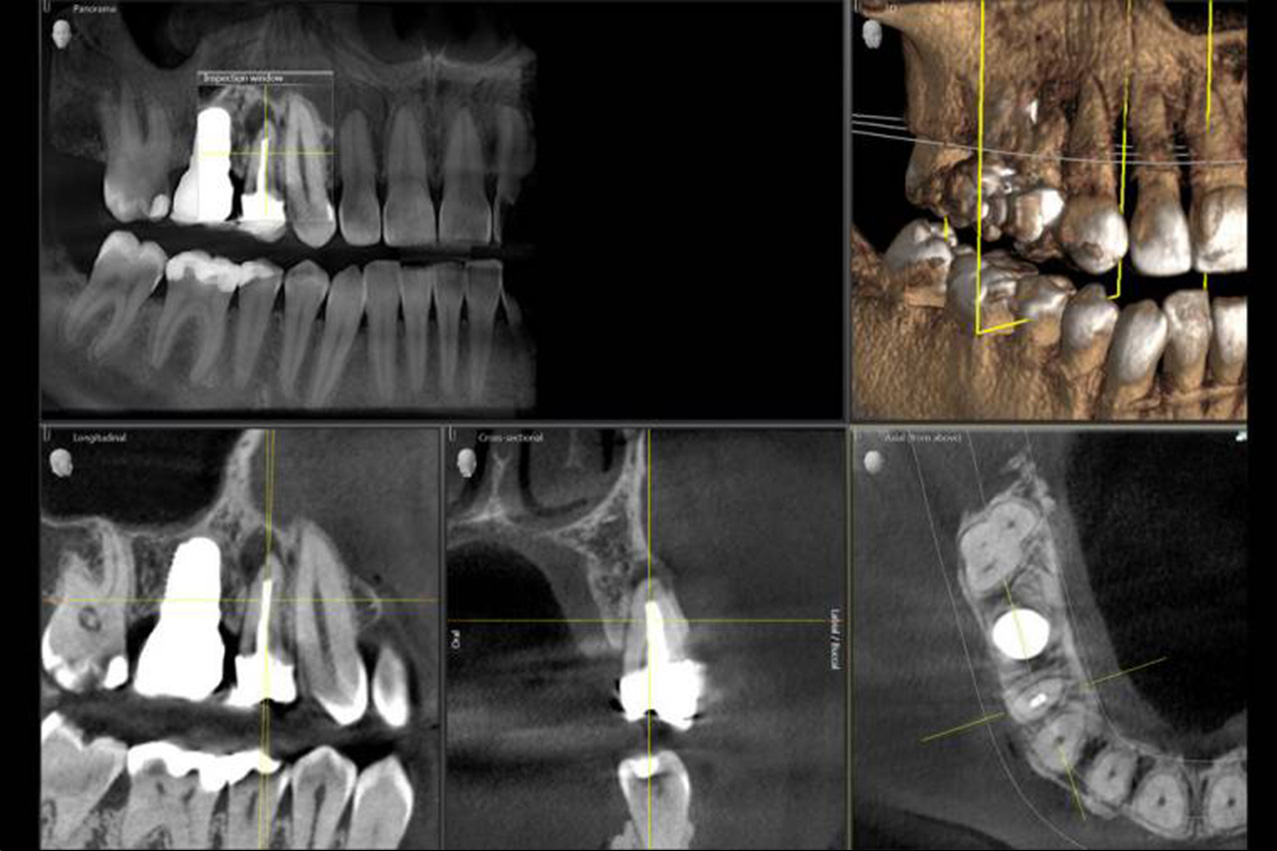

Die moderne Wurzelbehandlung (medizinisch Wurzelkanalbehandlung) ist ein häufiger Eingriff im Fachbereich der Endodontie (Lehre des Zahninneren) und hat zum Ziel, stabile aber erkrankte Zähne zu behandeln und sie damit langfristig zu erhalten. Eine Behandlung des Wurzelkanals ist notwendig, wenn Bakterien in das Innere eines Zahnes eingedrungen sind und dort eine schmerzhafte Entzündung verursacht haben. Um eine sichere Diagnose des Entzündungsherdes stellen zu können, ist neben der klinischen Untersuchung vor der Wurzelbehandlung auch die Anfertigung von Röntgenaufnahmen der Zähne und der Kieferknochen notwendig. So lassen sich durch den Einsatz fortschrittlicher und neuartiger Technologien wie die dreidimensionale digitale Volumentomographie (DVT) heutzutage Entzündungen an Zähnen bereits im Frühstadium sicher diagnostizieren.

Mit Hilfe der 3D-Röntgendiagnostik sind wir dadurch in der Lage, den genauen Entzündungsherd und das Ausmaß der Infektion zu lokalisieren und dabei die genaue Länge und Form der Wurzelkanäle dreidimensional zu erkennen, sodass eine gezielte Planung der anschließenden Wurzelbehandlung möglich ist. Neben dem Erhalt des natürlichen Zahnes hat die endodontische Behandlung (Wurzelkanalbehandlung) das Ziel, die dauerhafte Funktionsfähigkeit eines Zahnes zu sichern.

Durch die radiologische Nachkontrolle, die in der Regel frühestens 6 Monate nach einer Wurzelbehandlung bei einem zahnärztlichen Kontrolltermin erfolgt, können so nachträgliche Entzündungen an der behandelten Zahnwurzel sicher diagnostiziert werden. Bei unklaren Situationen, in denen jedoch eine eindeutige Diagnose durch zweidimensionale Röntgenbilder nicht möglich ist, lässt sich durch den Einsatz modernster Röntgentechnik mittels DVT und der 3D-Röntgendiagnostik eine Entzündung an der Wurzelspitze auf dreidimensionalen Röntgenbilder sicher feststellen.

Die Entzündung im oder aus dem Wurzelkanal heraus kann sich durch wiederkehrende Schmerzen oder Dauerschmerzen bemerkbar machen, die häufig bei Druck auf dem Zahn (Druckschmerz) oder bei dauerhafter Belastung des Zahnes (Belastungsschmerz) auftreten. Anderseits können Wurzelkanalentzündungen und Entzündungen an der Wurzelspitze (medizinisch apikale Parodontitis) häufig keine Beschwerden verursachen, sodass diese Infektionen erst am Röntgenbild oder mit Hilfe der dreidimensionalen Röntgenbildgebung DVT (digitale Volumentomographie) und der 3D-Röntgendiagnostik sicher erkannt werden können.

Wurzelkanäle können in ihrer Ausprägung unterschiedlich lang und krumm, stark verzweigt und oftmals unübersichtlich sein. Für die Revision einer Wurzelkanalbehandlung ist es daher unbedingt notwendig, die komplexe Anatomie der Wurzelkanäle und das Ausmaß der Infektion durch die Anfertigung einer 3D-Röntgenaufnahme sichtbar zu machen.